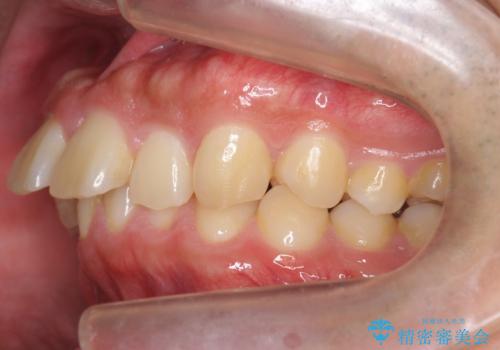

出っ歯を治したい 深いかみあわせ インビザラインで治療

- 前歯の前突を主訴に来院。

上の歯並びが前方にずれていました。

上顎は歯を抜かずに、奥歯を後ろに下げる治療を行っています。

下顎は歯列を拡大して並べました。